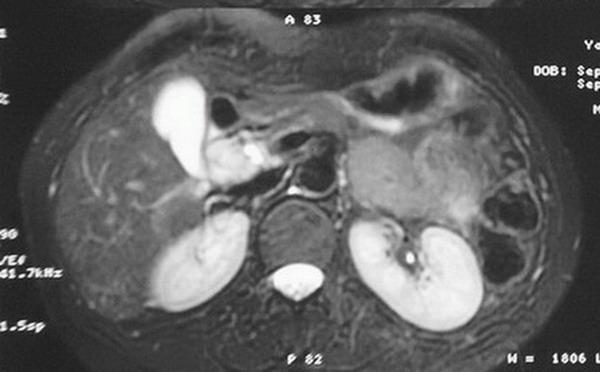

标题: MRI2066:腹膜后占位,请会诊,CT18531近期扫描图像

无明显不适,体检发现,

mri基本排除血管类肿瘤,明显强化说明极富血供,临床无症状,考虑胰岛细胞瘤可能大。

强化明显,并见有血管与之相连;考虑巨淋巴增生症.

极富血供的占位性病变,首先考虑良性,期待结果。